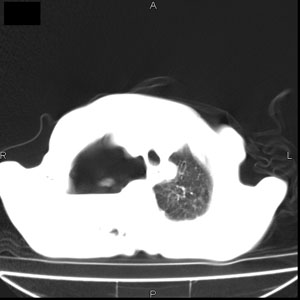

患者男,77岁,于3日前从树上摔下,头部查ct示蛛血,硬膜下出血,上腹部ct未见明显异常,右侧胸腔积液,左侧如常。肺部拍片示右侧肋骨多发骨折住院后今日来查肺部ct,我看到的是1。右侧胸腔血气胸并右肺上叶,中叶压缩性肺不张,2。右肺下叶肺挫伤并多发肋骨骨折,肌内及皮下积气3。左侧少量胸腔积液,我想请教的是3天前左侧胸腔里没有积液今天怎么出现了呢,是什么原因呢?请讨论。